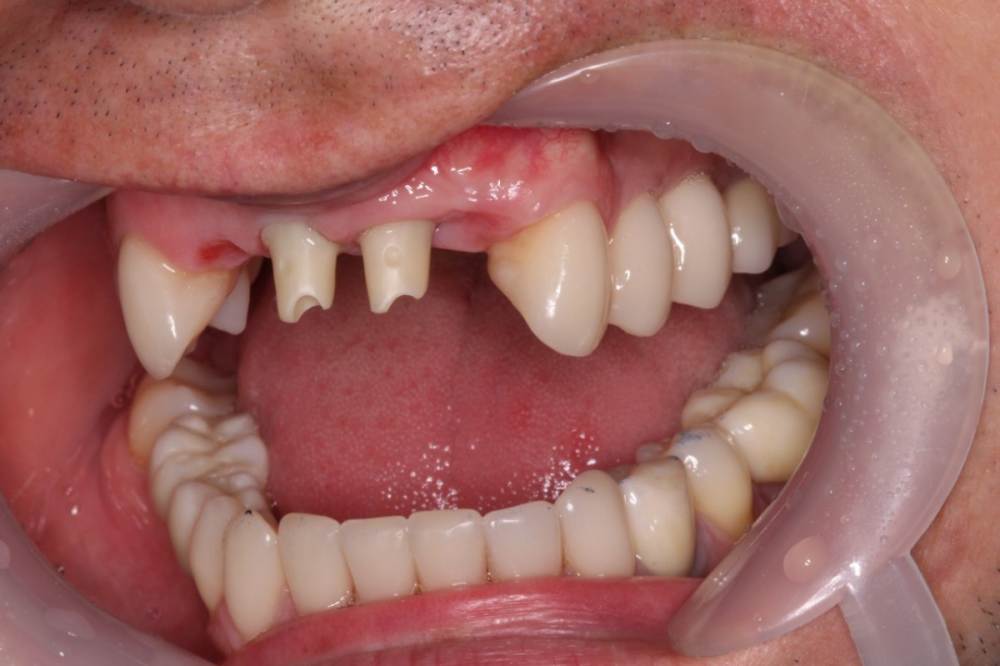

maksimstom Опубликовано 27 октября, 2020 Поделиться Опубликовано 27 октября, 2020 Добрый день, коллеги. Подскажите как бы поступили. 1,5 мес назад удалены зубы 1.2-2.2, установлены импл 11,21, сст вестибулярного 1.2-2.2. Фото до и после прилагаются(рг фото при необходимости добавлю, на работе осталось) в плане 1,5мес ждать пока заживет десна , далее что-то думать, склоняюсь к Сузуки, мб несколько этапов. Ссылка на комментарий

колесников Опубликовано 27 октября, 2020 Поделиться Опубликовано 27 октября, 2020 Здравствуйте! Во первых что это за фрагмент белеет? Во вторых нужно подкорректировать реставрацию и пропилить пространство для сосочков. Далее я бы добавил сст в расщеплённый лоскут ,(разрез с гребня отступя небнее,как бы сместить ткани вестибулярно )и сделать овоид на 22ом. ( Там явно костный дефект -это вершина треугольника. Сосочки 21,23-это основание. Основание будет стремиться к вершине. ) Чере 2 недели после снятия швов применять ирригатор. Оставить созревать на 1,5-2мес. По итогу ,решать о пластике сосочка 21-22 по масана. PS. 11 шахта вестибулярно,надеюсь там есть балкон,иначе десневой контур улетит апекально. Ссылка на комментарий

maksimstom Опубликовано 28 октября, 2020 Автор Поделиться Опубликовано 28 октября, 2020 Белеет кость, во время операции перекрывал ее сст от 23 до 11 с небольшой надеждой на то что запитается) наверно отвалится скоро. Положение импл из-за анатомии гребня, балкон есть. Спасибо за совет, наверно так и поступлю, но думаю подождать все-таки месяц пусть десна созреет Ссылка на комментарий

колесников Опубликовано 28 октября, 2020 Поделиться Опубликовано 28 октября, 2020 Белеет кость, во время операции перекрывал ее сст от 23 до 11 с небольшой надеждой на то что запитается) наверно отвалится скоро. Положение импл из-за анатомии гребня, балкон есть. Спасибо за совет, наверно так и поступлю, но думаю подождать все-таки месяц пусть десна созреет даже не знаю что сказать. Эстетический прогноз серьезный. Оголенный фрагмент секвестрируется 1 Ссылка на комментарий